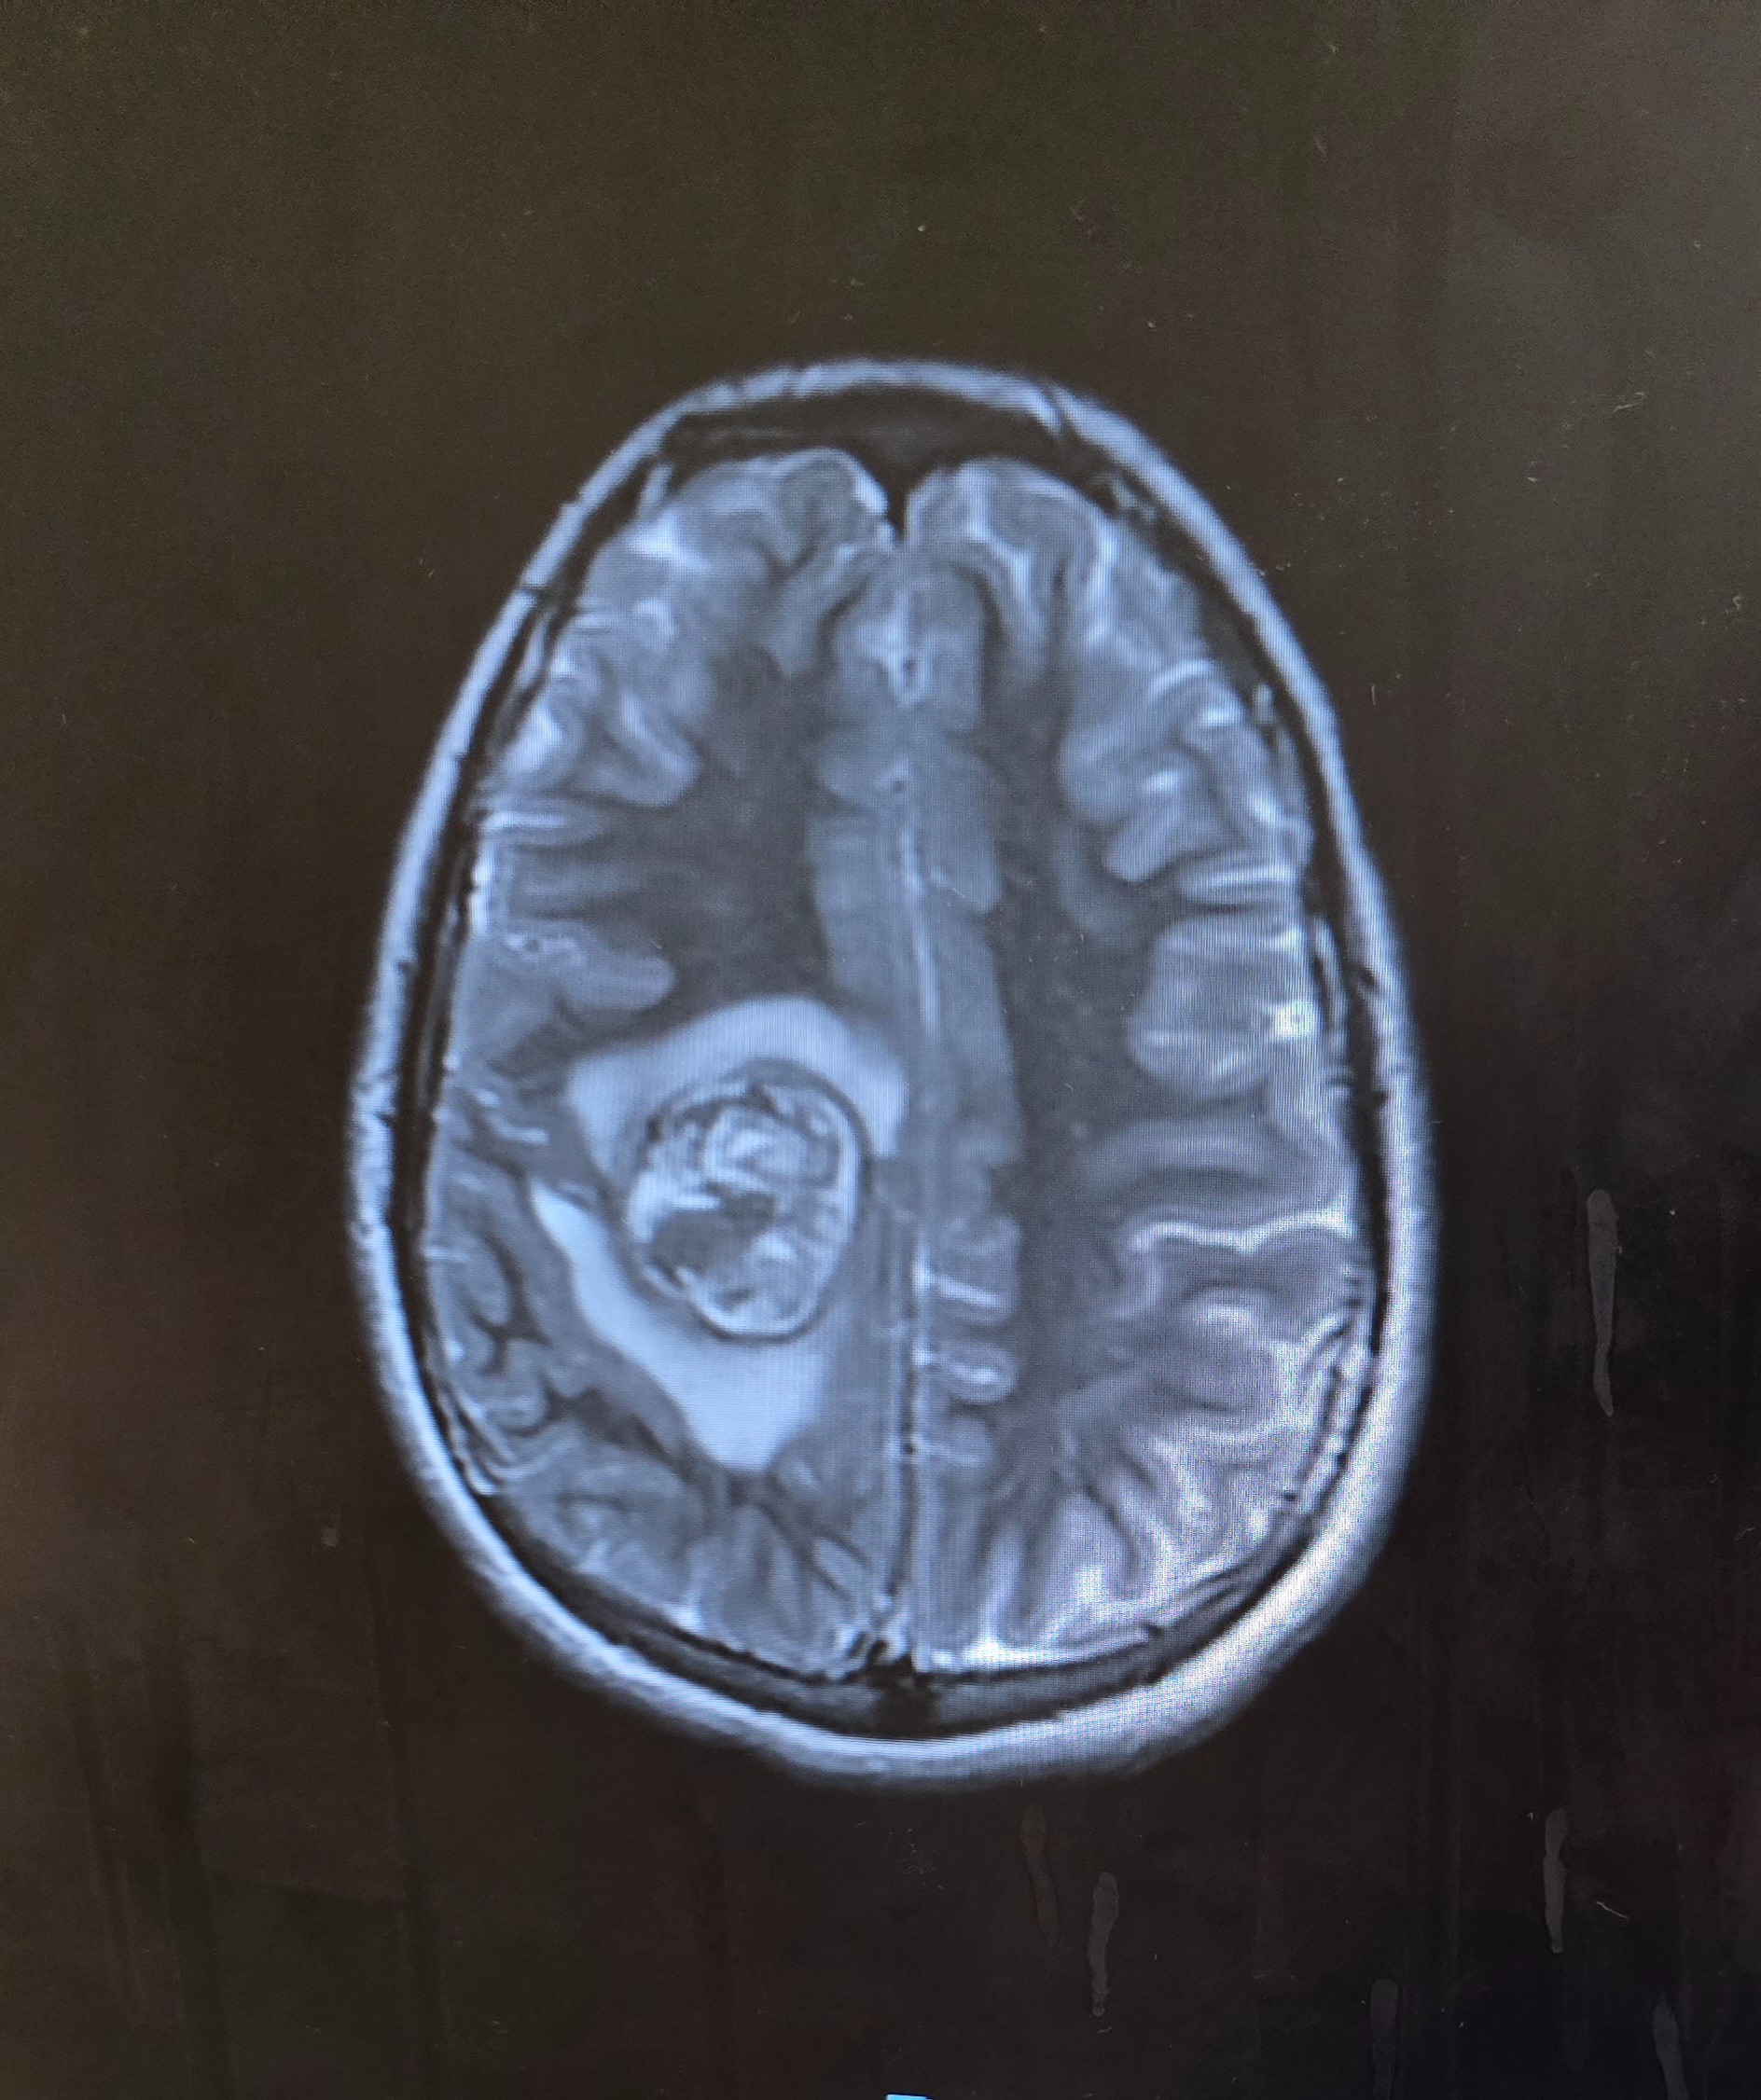

Our world has been turned upside down. Our 13-year-old son, Mason, has recently been diagnosed with a very large 4.3 cm mass in his brain with significant swelling that has hemorrhaged and is now facing brain surgery on January 7th.

No child should ever have to endure something like this, and no parent should have to watch their child go through this. Within a week's time span, Mason lost all movement and control of the left side of his body. He was rushed to multiple doctors before finally getting some answers. He has a Cavernoma. It is an abnormal cluster of blood vessels with slow-flowing blood. This is what causes the neurological symptoms he is having.